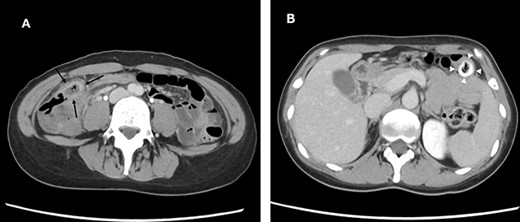

Laparoscopic findings showed that the inflammatory changes were not significant. The surgeon had expertise skills on multiport laparoscopic surgery (MLS) with some SILS experience. Initially, a 40-mm incision was made at the umbilicus. We then performed ileocolic mobilization and lymphadenectomy with ileocolic arterial and venous resection by SILS, similar to MLS (Fig. 3A). Functional end-to-end anastomosis was performed out of the body after removal through an umbilical incision (Fig. 3B and C). The operation time was 2 h and 47 min, and the amount of bleeding was minimal. Macroscopic findings of the surgical specimen showed a diverticulum with an ulcer in the cecal colon, but no fecalith (Fig. 4). Pathological findings showed deep ulceration and abscess formation with no malignant findings. The patient’s course was good, and she was discharged 8 days after the operation.

Macroscopic findings of the surgical specimen showing a diverticulum with an ulcer in the cecal colon (white arrowheads) and no fecalith (black arrows).